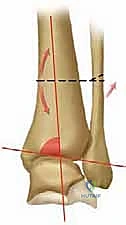

2. التصوير بالأشعة السينية بوضعية الوقوف (Weight-bearing X-rays)

هذا هو حجر الأساس في التشخيص. الأشعة العادية والمريض مستلقٍ لا تظهر الحجم الحقيقي للتشوه. يطلب الدكتور هطيف صوراً خاصة والمريض يحمل وزنه كاملاً على قدميه.

* المنظر الأمامي الخلفي (AP View): لتقييم المسافة المفصلية وتحديد زاوية سطح الساق (Tibial Anterior Surface Angle - TAS).

* منظر سالتزمان (Saltzman View): وهو منظر إشعاعي متخصص جداً لتقييم محاذاة الكعب الخلفي بالنسبة لمحور الساق، وهو أمر حاسم في التخطيط الجراحي.